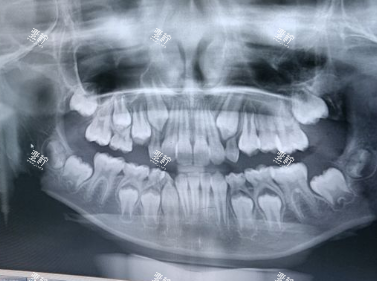

杜小润医生会要求患者先做CBCT和口腔全景片,重点看三个指标:牙槽骨高度(需≥8mm)、宽度(需≥5mm)、密度(骨密度T值≥-2.5)。

口腔ct

比如有位患者骨密度T值-3.0(骨质疏松),杜医生建议先做骨增量手术,而不是直接种牙。

检查清单:血常规、凝血功能、传染病筛查(乙肝、梅毒、HIV),确保种植靠谱。